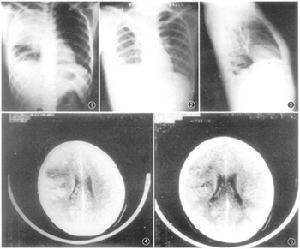

3 胸部X線檢查:肺葉或肺段分布的均勻緻密的大片狀實變陰影可確診。

胸部X線檢查都會顯示肺浸潤,但在最初數小時可表現不明顯或難以發現。支氣管肺炎是最常見的X線表現,但實變局限於一葉的大葉性肺炎伴典型支氣管充氣征是肺炎球菌感染的特殊表現。

嚴重且可能導致死亡的併發症為進展性肺炎,有時伴有成人呼吸窘迫綜合徵和/或膿毒性休克。胸部X線檢查可發現約25%的病人有胸膜滲出,且僅1%左右的病人有膿胸。有些病人產生病變鄰近部位的感染(如膿胸或化膿性心包炎)。菌血症可造成肺以外的感染病灶,包括膿毒性關節炎,心內膜炎,腦膜炎及腹膜炎(腹水病人)。有些病人出現肺部重複感染,表現為在治療過程中,暫時改善之後又出現發熱和新的肺浸潤而致病情惡化。

一般主張對35歲以上的病人進行隨訪X線檢查。胸部X線檢查可能要在幾周之後才能看到浸潤消散,病情嚴重及有菌血症或原先已有慢性肺病的病人尤其如此。治療開始後6周或6周以上仍然有浸潤,表明可能有原發性支氣管新生物或TB。